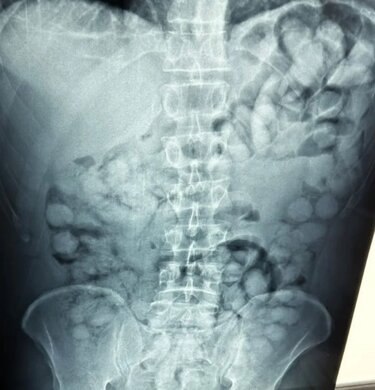

Ένας άνδρας, από τη Βραζιλία, συνελήφθη σήμερα το πρωί στο αεροδρόμιο «Ελ. Βενιζέλος», κατηγορούμενος ότι είχε καταπιεί σημαντική ποσότητα κοκαΐνης.

Σύμφωνα με την ΕΛΑΣ, ο άνδρας έφτασε στην Αθήνα, μέσω Παρισιού και στον έλεγχο που διενεργήθηκε, διαπιστώθηκε ότι είχε καταπιεί περίπου 100 συσκευασίες κοκαΐνης.